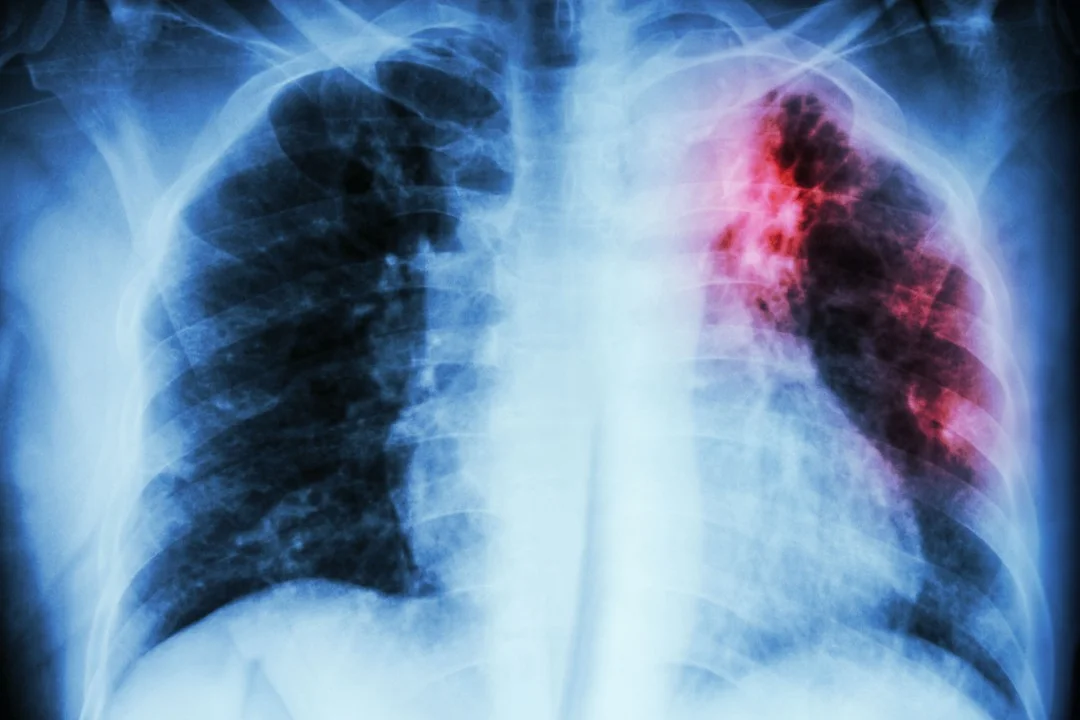

UK Health Security Agency data show tuberculosis cases rose in recent years, with 5,424 cases in 2025 (up 25% from 2022), though 2024 had the highest total at 5,480; the disease mainly attacks the lungs and is linked to poverty, with the North East seeing the strongest rise; 65 drug-resistant TB cases were reported; experts urge rapid diagnosis and treatment to curb spread, noting TB’s historic toll on figures like Emily Brontë and George Orwell.